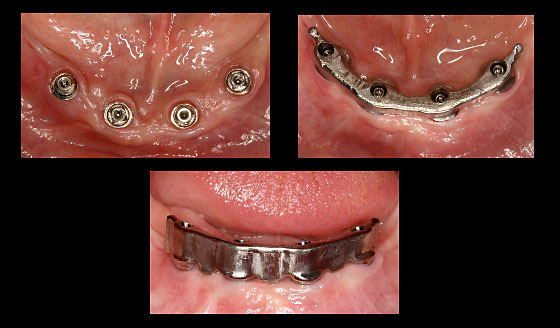

Fall: Implantatgetragene Stegarbeit bei zahnlosem Unterkiefer

Implantate Unterkiefer und vorbereiteter Abdrucklöffel

Anprobe des Stegs

Steganprobe

Ausgearbeiteter Steg und Anpassung der Unterkieferprothese

Eingegliederter Steg

Schlussbild - Implantatgetragene Unterkieferprothese